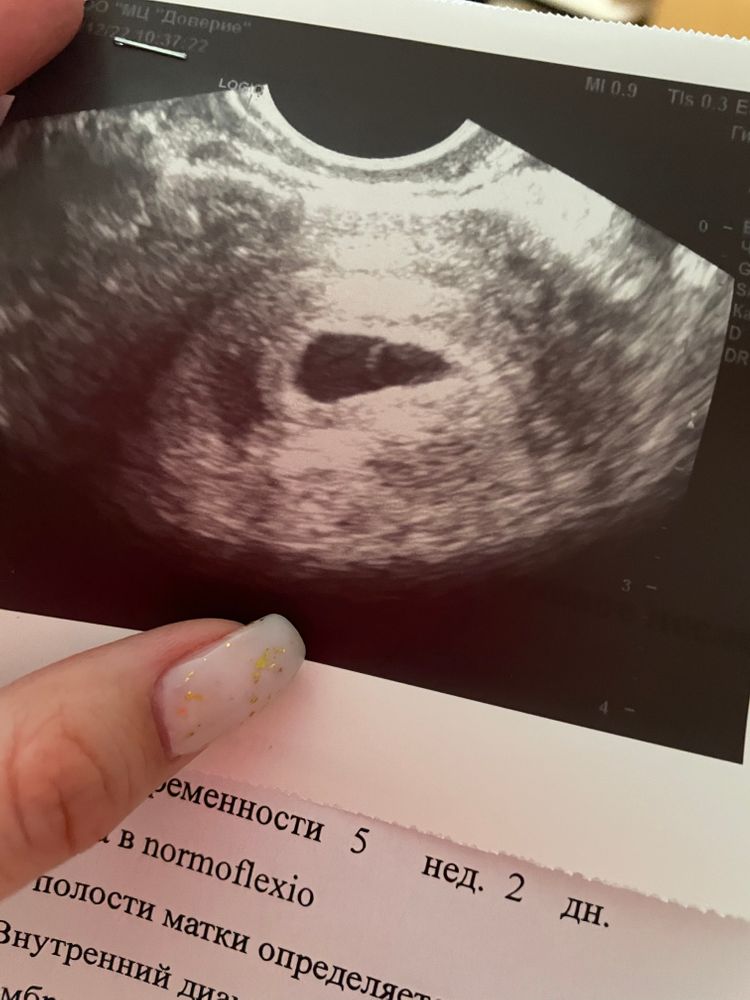

Чёрная капля это плодное яйцо, кружок внутри-желточный мешок. Мне кажется и эмбриончик уже видно)

Это жм, как пузырик) где-то на краешке пузырика может уже прятаться эмбриончик, но он пока маленький)

Настя, а сама темная капелька, внутри которой он - это пя

Темное образование овально- треугольной формы - плодное яйцо, внутри белок округлое образование- желточный мешок